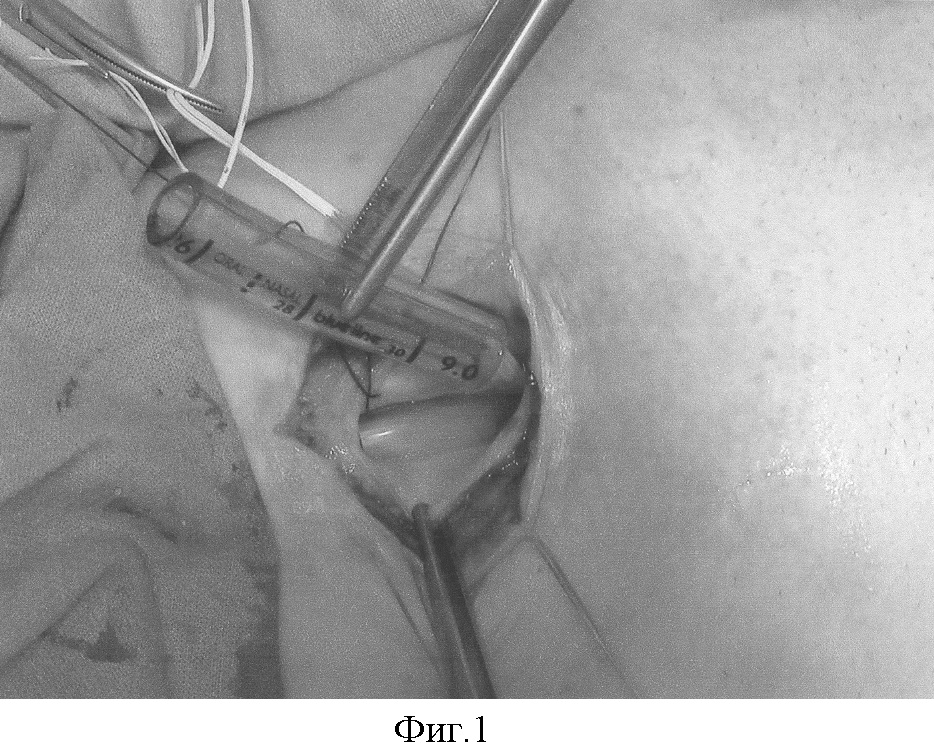

Фиг.4 – фрагменты хряща в виде дуг уложены на поверхностную фасцию в проекции питающих сосудов в сформированные отдельные ложа с сохранением между ними перегородок с перфорантными сосудами. Фрагменты хряща фиксированы швами к коже аутотрансплантата. Свободный реваскуляризируемый аутотрансплантат в едином комплексе с фрагментами хряща поднят на сосудистой ножке.